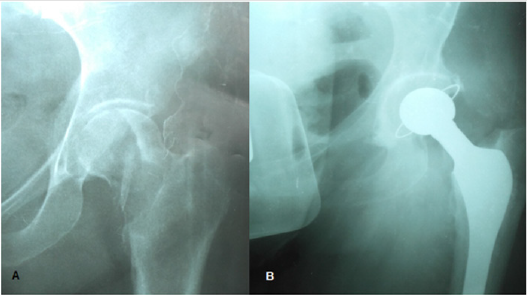

Figure 7:

A. Giant Cell Tumor at the epiphyseal level of the left hip.

B. Total prosthetic hip replacement.